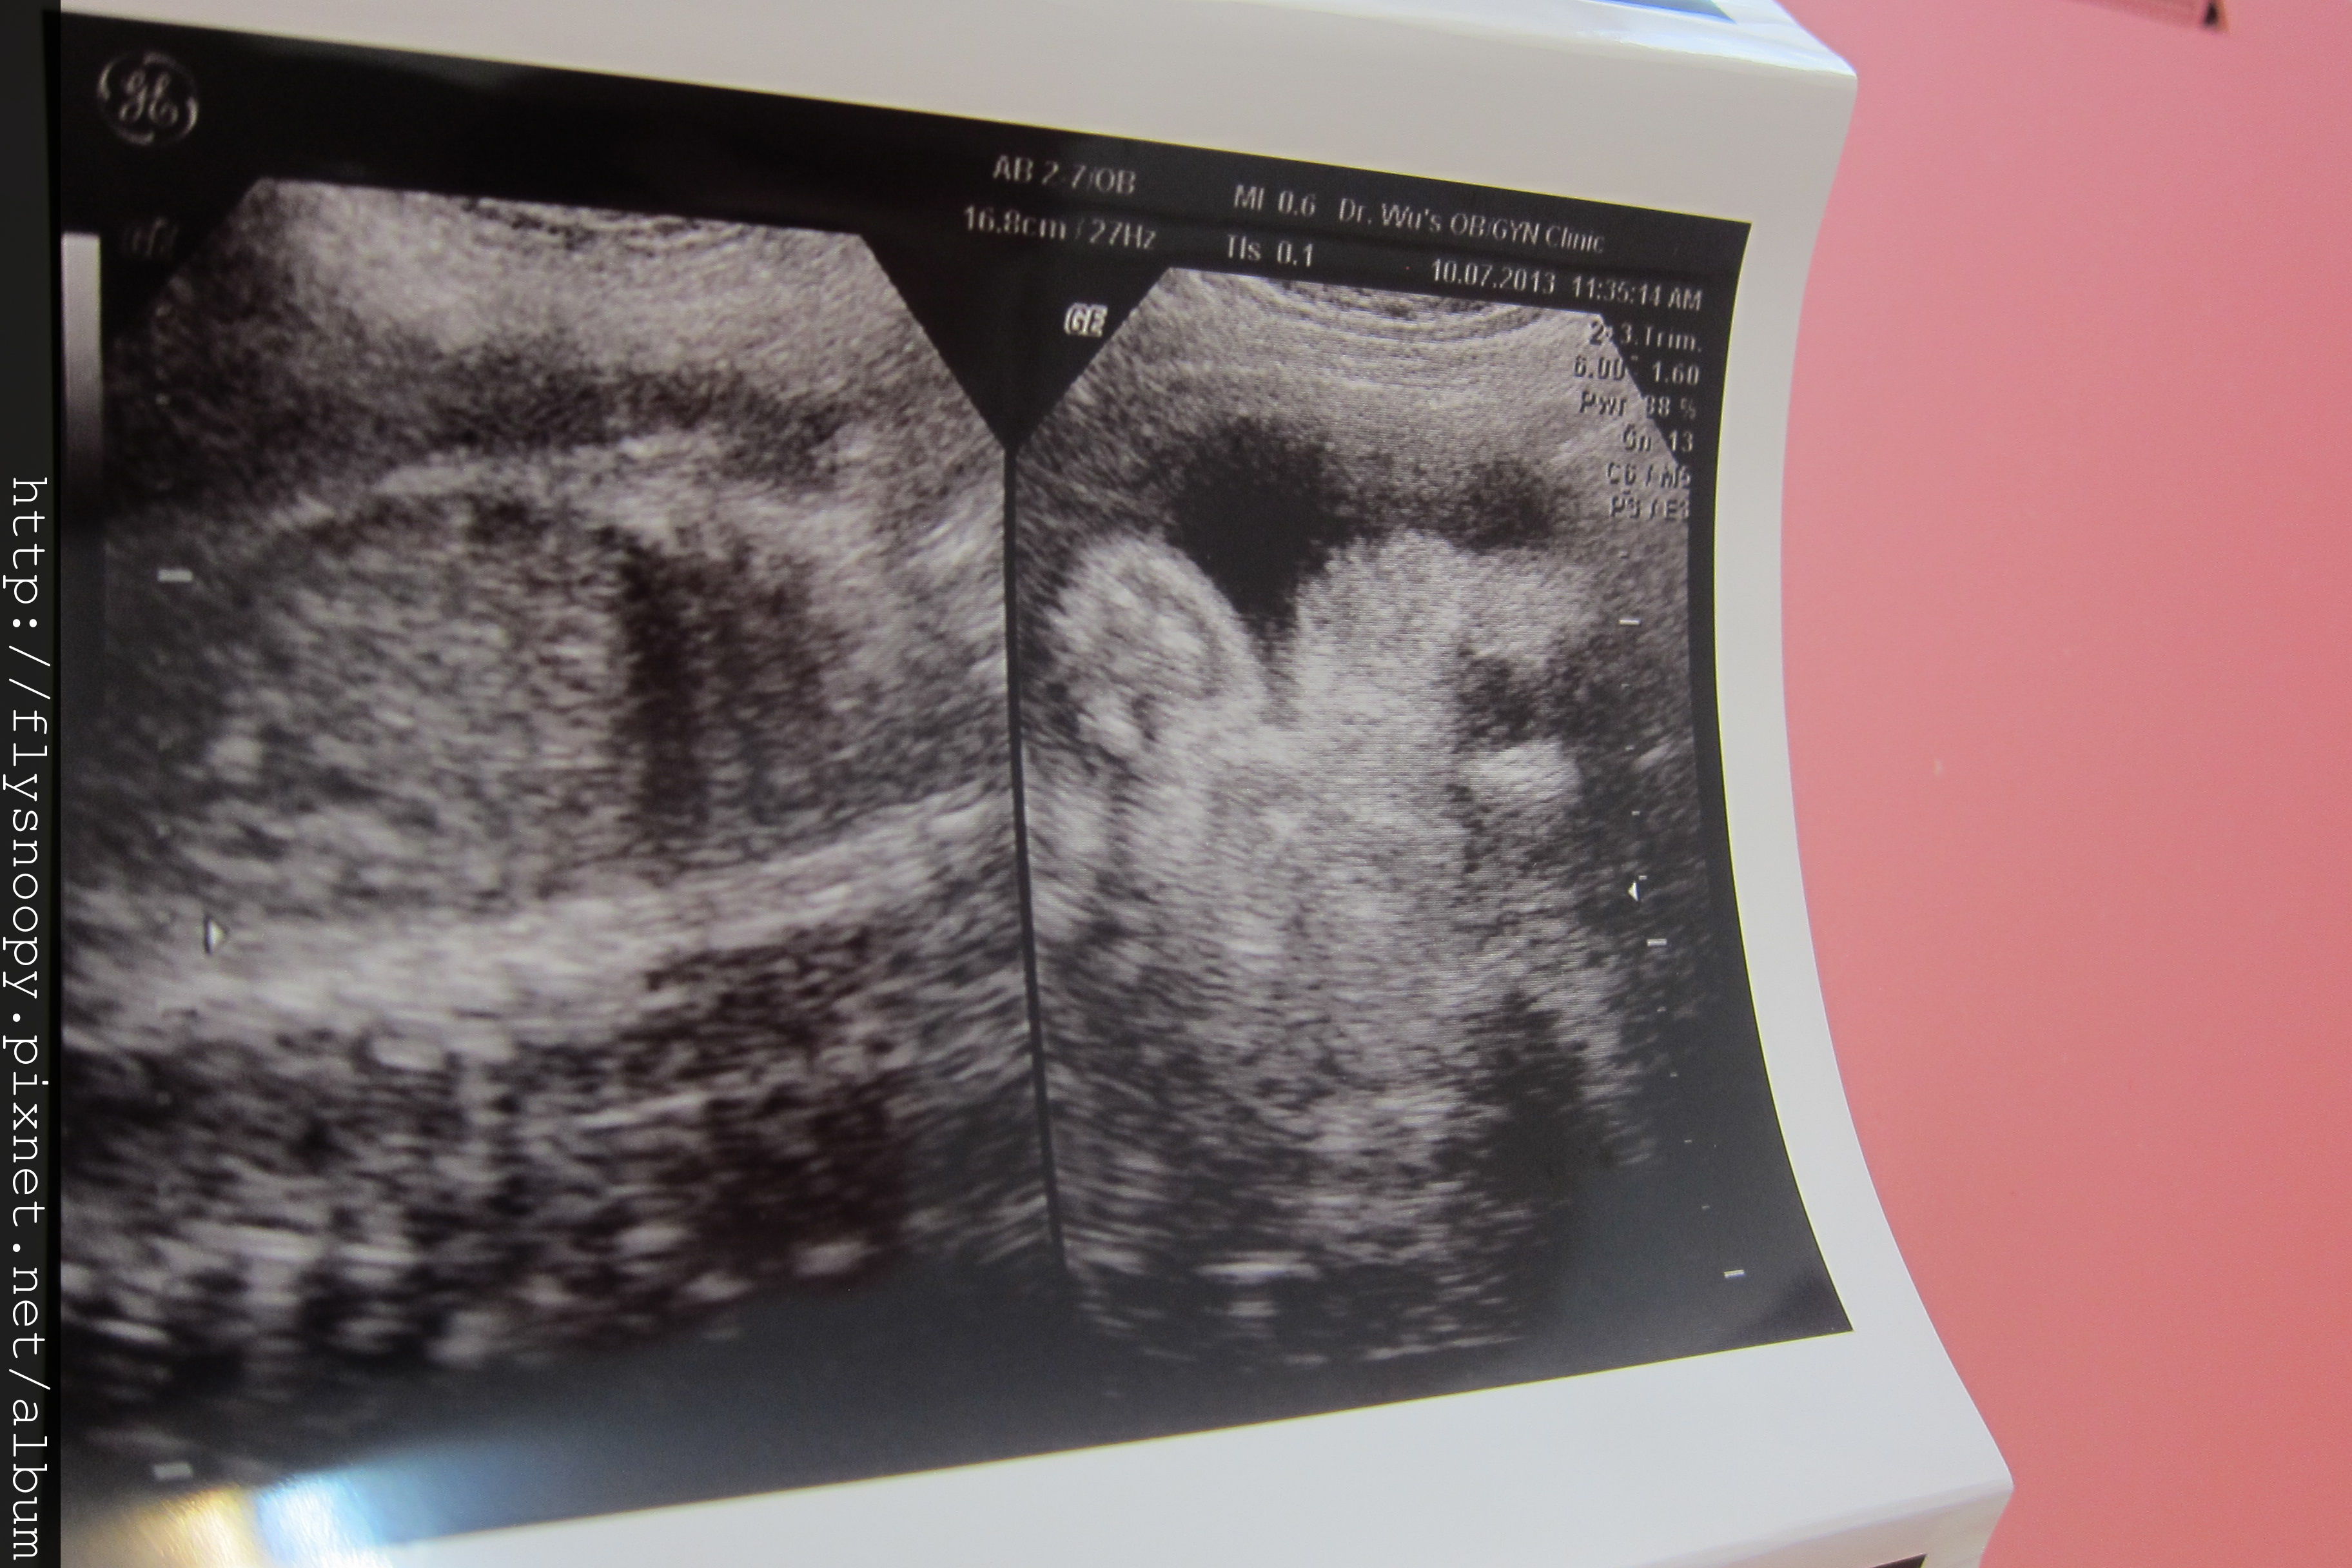

7/24 第8次產檢

這次一樣是早上去醫院,因為晚上人實在是好多,都要等很久

第八次產檢記錄

體重:63.5

血壓:105/67

尿糖、尿蛋白:正常

EFW:2003(突破2000囉~~~~~)